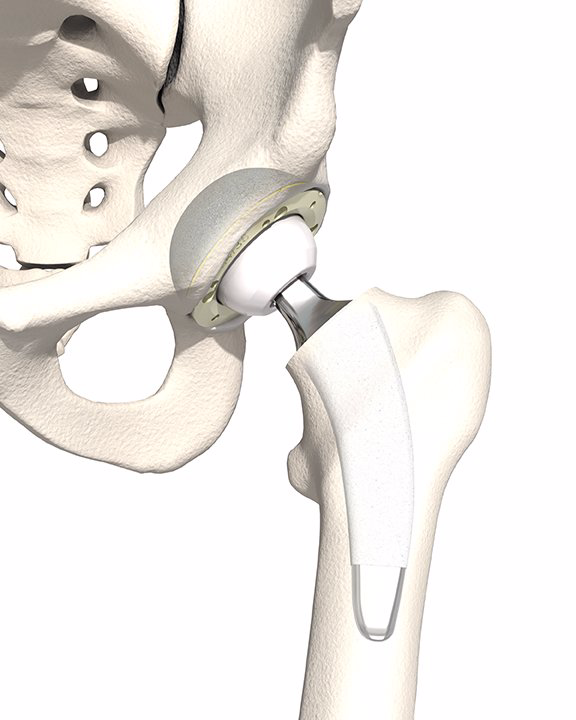

Die Hüftprothese ist zweifellos eine der erfolgreichsten orthopädischen Operationen des Jahrhunderts. Hohe Lebensqualität und lange Standzeiten des Implantates bei den meisten Patienten sind die Gründe dafür. Bei Einrissen der Gelenklippe (Labrum) oder Knochenhöcker an Pfanne oder Schenkelhals kann eventuell eine Hüftarthroskopie zielführend sein.

Ein zufriedenstellendes Ergebnis bedeutet im Hinblick auf das künstliche Hüftgelenk eine volle Wiederherstellung der Mobilität inklusive Sportfähigkeit.